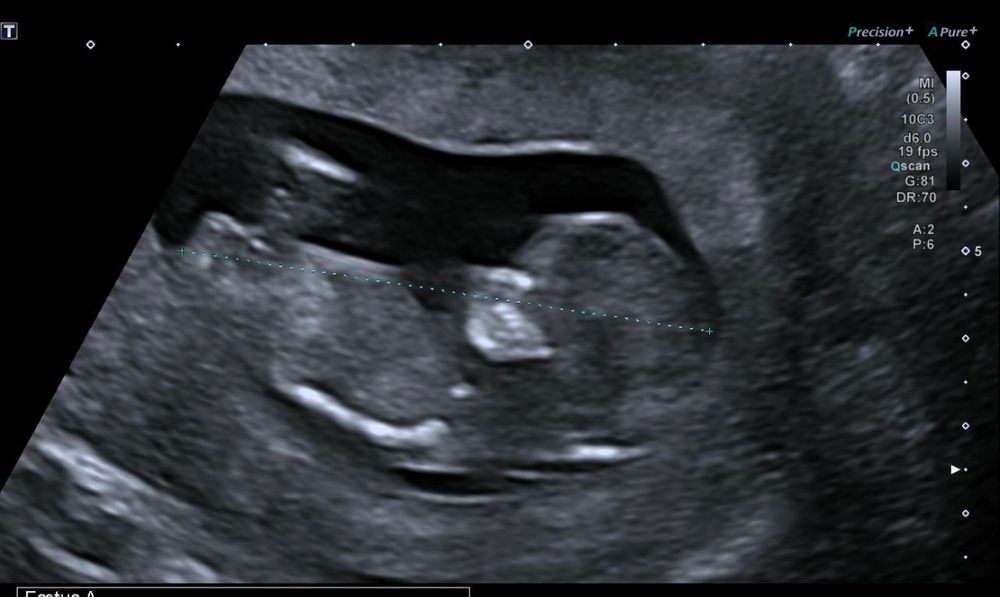

Divaluba, Изображение Поздравляю! 🌸🌸🌸 вот просто сравниваю, вот мой малыш на узи 12 н.5д)) кажется, что снова девочка, но Надежда не покидает)) бугорок расположен параллельно позвоночнику!))

12.05.2022

Emili, девочка😍

23.05.2022